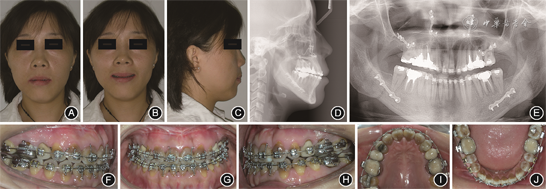

成年患者正颌术后5个月时面像、口内像和影像学资料 A:正面像;B:正面微笑像;C:侧面像;D:头颅侧位X线片;E:曲面体层X线片;F:右侧

像;G:正面

像;H:左侧

像;I:上颌

面像;J:下颌

面像

(3)术后正畸治疗:正颌术后2个月,尖牙、磨牙基本为远中关系,前牙覆

覆盖较浅,行双侧Ⅲ类颌间牵引,维持上下牙咬合关系;术后5~6个月,双侧前牙区及磨牙区行颌间“8”字牵引,调整咬合关系(图5);术后7~12个月,33—43邻面去釉3次,斜行牵引调整中线,颌间弹力牵引调整咬合关系,使用摇椅弓改善覆

覆盖关系;术后13个月(矫治28个月),牙齿排列整齐,咬合关系正常,拆除固定矫治器,上下颌戴压膜保持器(图6)。